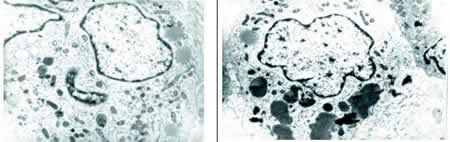

电镜检查(见图4):电镜下见诸多组织细胞样细胞,其细胞核不规则,核周有中间丝包绕,胞质内线粒体丰富,体积小,粗面内质网也多见,多聚核糖体散在分布,另见脂滴或脂质成分。有的细胞内见多个异样物,体积大,直径约2 μm的,并有双层膜包绕,其内含有多个线粒体,有的见类核样物。还可见丝状物或小泡样结构。据推测,这些异样物并不像自噬泡,而是吞噬物。所见切片细胞中未找到Birbeck颗粒。